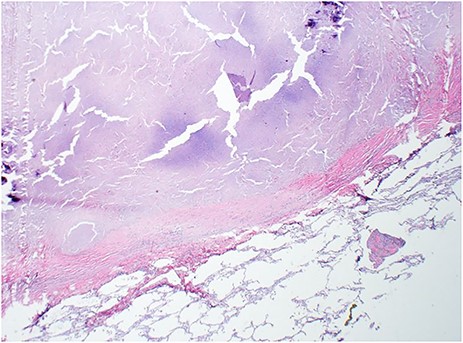

H&E of left lung nodule from wedge resection with hyalinized necrotizing granuloma and surrounding normal lung parenchyma (2×).

A 58-year-old man with idiopathic pulmonary fibrosis listed for lung transplantation received a donor lung offer from a 46 year old non-smoking brain dead female donor. Prior to us receiving the offer, the donor lungs had been rejected by three other centers. The Lung Allocation Score for their three recipients ranged from 51.4 to 89.87. The donor blood gasses revealed excellent oxygenation with a PaO2 of 567 mmHg. Chest radiograph, however, revealed a large calcified mass confirmed on computed tomography (CT) as a 3 cm × 3 cm mass in the left lower lobe of the lung (Fig. 1). CT imaging of the abdomen and pelvis revealed a cystic right ovarian lesion measuring 7.3 cm × 4.2 cm × 4.8 cm. The presence of large pulmonary and ovarian masses created initial doubt and hesitation about the safety of using the lungs for transplantation. Due diligence was exercised and discussions were conducted with multiple team members and radiologists. Radiologic appearance of both (pulmonary and ovarian) masses was deemed to be benign and the lungs were accepted. Ovarian biopsy at procurement confirmed a benign mucinous cystadenoma. Bilateral sequential lung transplantation was performed along with backtable wedge resection of left lower lobe lung mass prior to implantation of the left lung. Grossly, the cut surface of the mass had a chalky white appearance. (Fig. 2) Histopathologic examination revealed the pulmonary mass to be a benign hyalinized necrotizing granuloma. (Fig. 3) Postoperatively, the patient did well with no evidence of primary graft dysfunction. More than 1 year after the transplant, the recipient continues to do well with excellent functional status without any evidence of chronic lung allograft dysfunction.